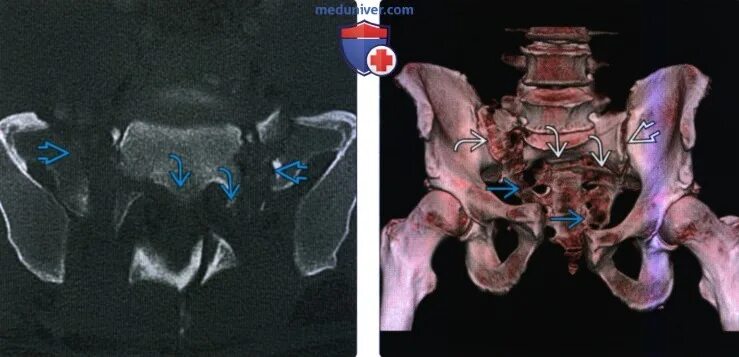

Стресс-перелом боковых масс крестца мрт. перелом боковых масс крестца.

Перелом крестцового отдела позвоночника. стресс-перелом боковых масс крестца мрт. перелом s3 позвонка крестца. перелом крестца позвонка s5.

Перелом боковых масс крестца. вертикальный перелом боковой массы крестца. классификация переломов креста. перелом латеральной части крестца.

Перелом боковой массы крестца справа. перелом правых боковых масс крестца со смещением. остеосинтез перелом боковых масс крестца.